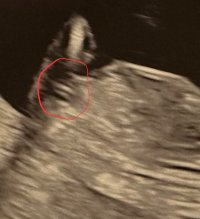

trodde kanskje det var noe ) se hvor jeg har satt ring på bildet hihi